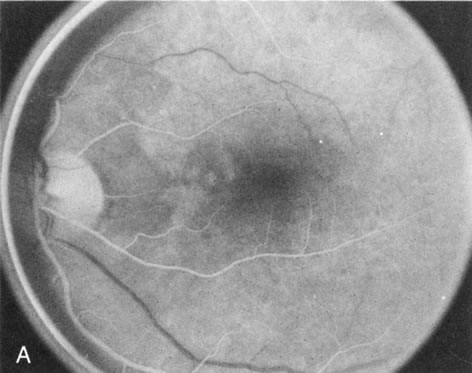

Choroideremia

In the early stages of choroideremia, before choroidal atrophy is funduscopically obvious and when the picture resembles RP, FA indicates diffuse choroidal atrophy throughout the entire retina. Only the macular area remains preserved (Fig. 4A and B).

Fig. 4. Choroideremia and choroideremia carrier. A. The choroidal atrophy in this affected male is not apparent in the fundus. B. However, the angiogram shows diffuse atrophy of the choriocapillaris with persistent visualization of the larger choroidal vessels. C. This carrier female has peripapillary choroidal atrophy and diffuse pigment mottling. D. The patchy areas of focal choroidal atrophy that occasionally occurs in carriers is evident on angiography.

The typical carrier female, with focal or diffuse pigment mottling, does not show choroidal atrophy. However, a few carrier females have a more severe form with focal areas of choroidal atrophy. The presence of these areas, and possible progression, can be documented by FA (Fig. 4C and D). These carriers exhibit a mosaicism, which is explained by the Lyon hypothesis of random X-chromosome inactivation.